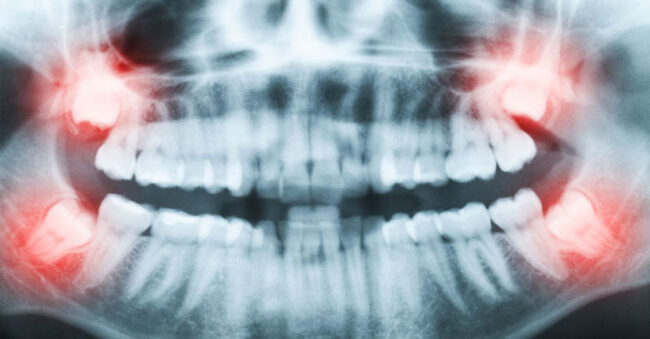

Dental Implants for Missing Teeth: Permanent, Natural-Looking Solutions Dental implants are the gold standard for replacing missing teeth, restoring both function and aesthetics with long-lasting results. As advanced tooth replacement solutions, dental implants provide exceptional stability for crowns, bridges, and implant-supported dentures—helping you regain a confident, natural-looking smile. Dental implants are small, biocompatible titanium posts…